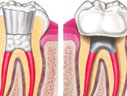

Popularmente conhecida como tratamento de canal, consiste na remoção do nervo e descontaminação das paredes internas e obturação da raiz.

Clique na imagem para ampliar: